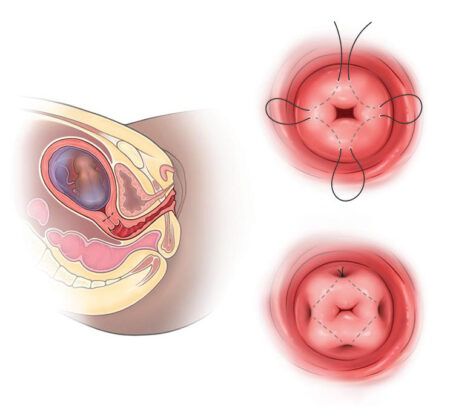

الخِياطة العنقية (السيركلاج)

السيركلاج:

السيركلاج هو إجراء يتم فيه خياطة عنق الرحم لدى النساء الحوامل بهدف تقويته وزيادة قدرته على التحمل، ومنع حدوث مضاعفات ناتجة عن قصور عنق الرحم.

تقنية الإجراء:

- بعد تطهير المهبل وعنق الرحم، وتخدير قصير، يُمسك عنق الرحم بملاقط، ثم يُخاط على بعد 2 سم على الأقل فوق الفتحة الخارجية للعنق باستخدام إبرة منحنية وخيط سميك غير قابل للامتصاص، ويُربط حول عنق الرحم.